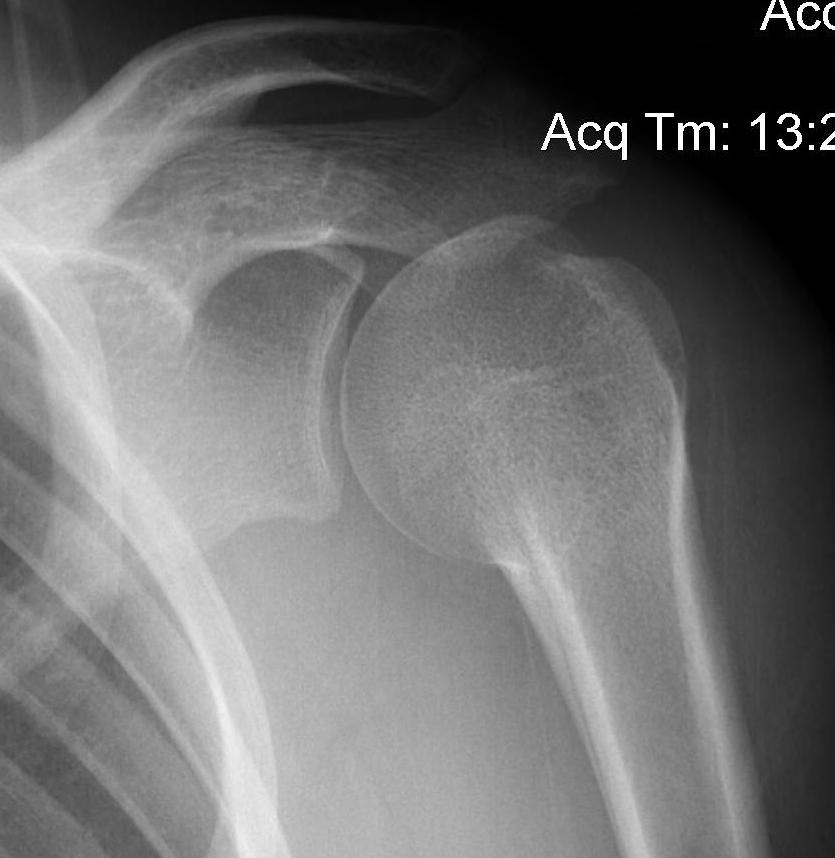

Case: 16 year old boy

Initial injury 18 months post injury